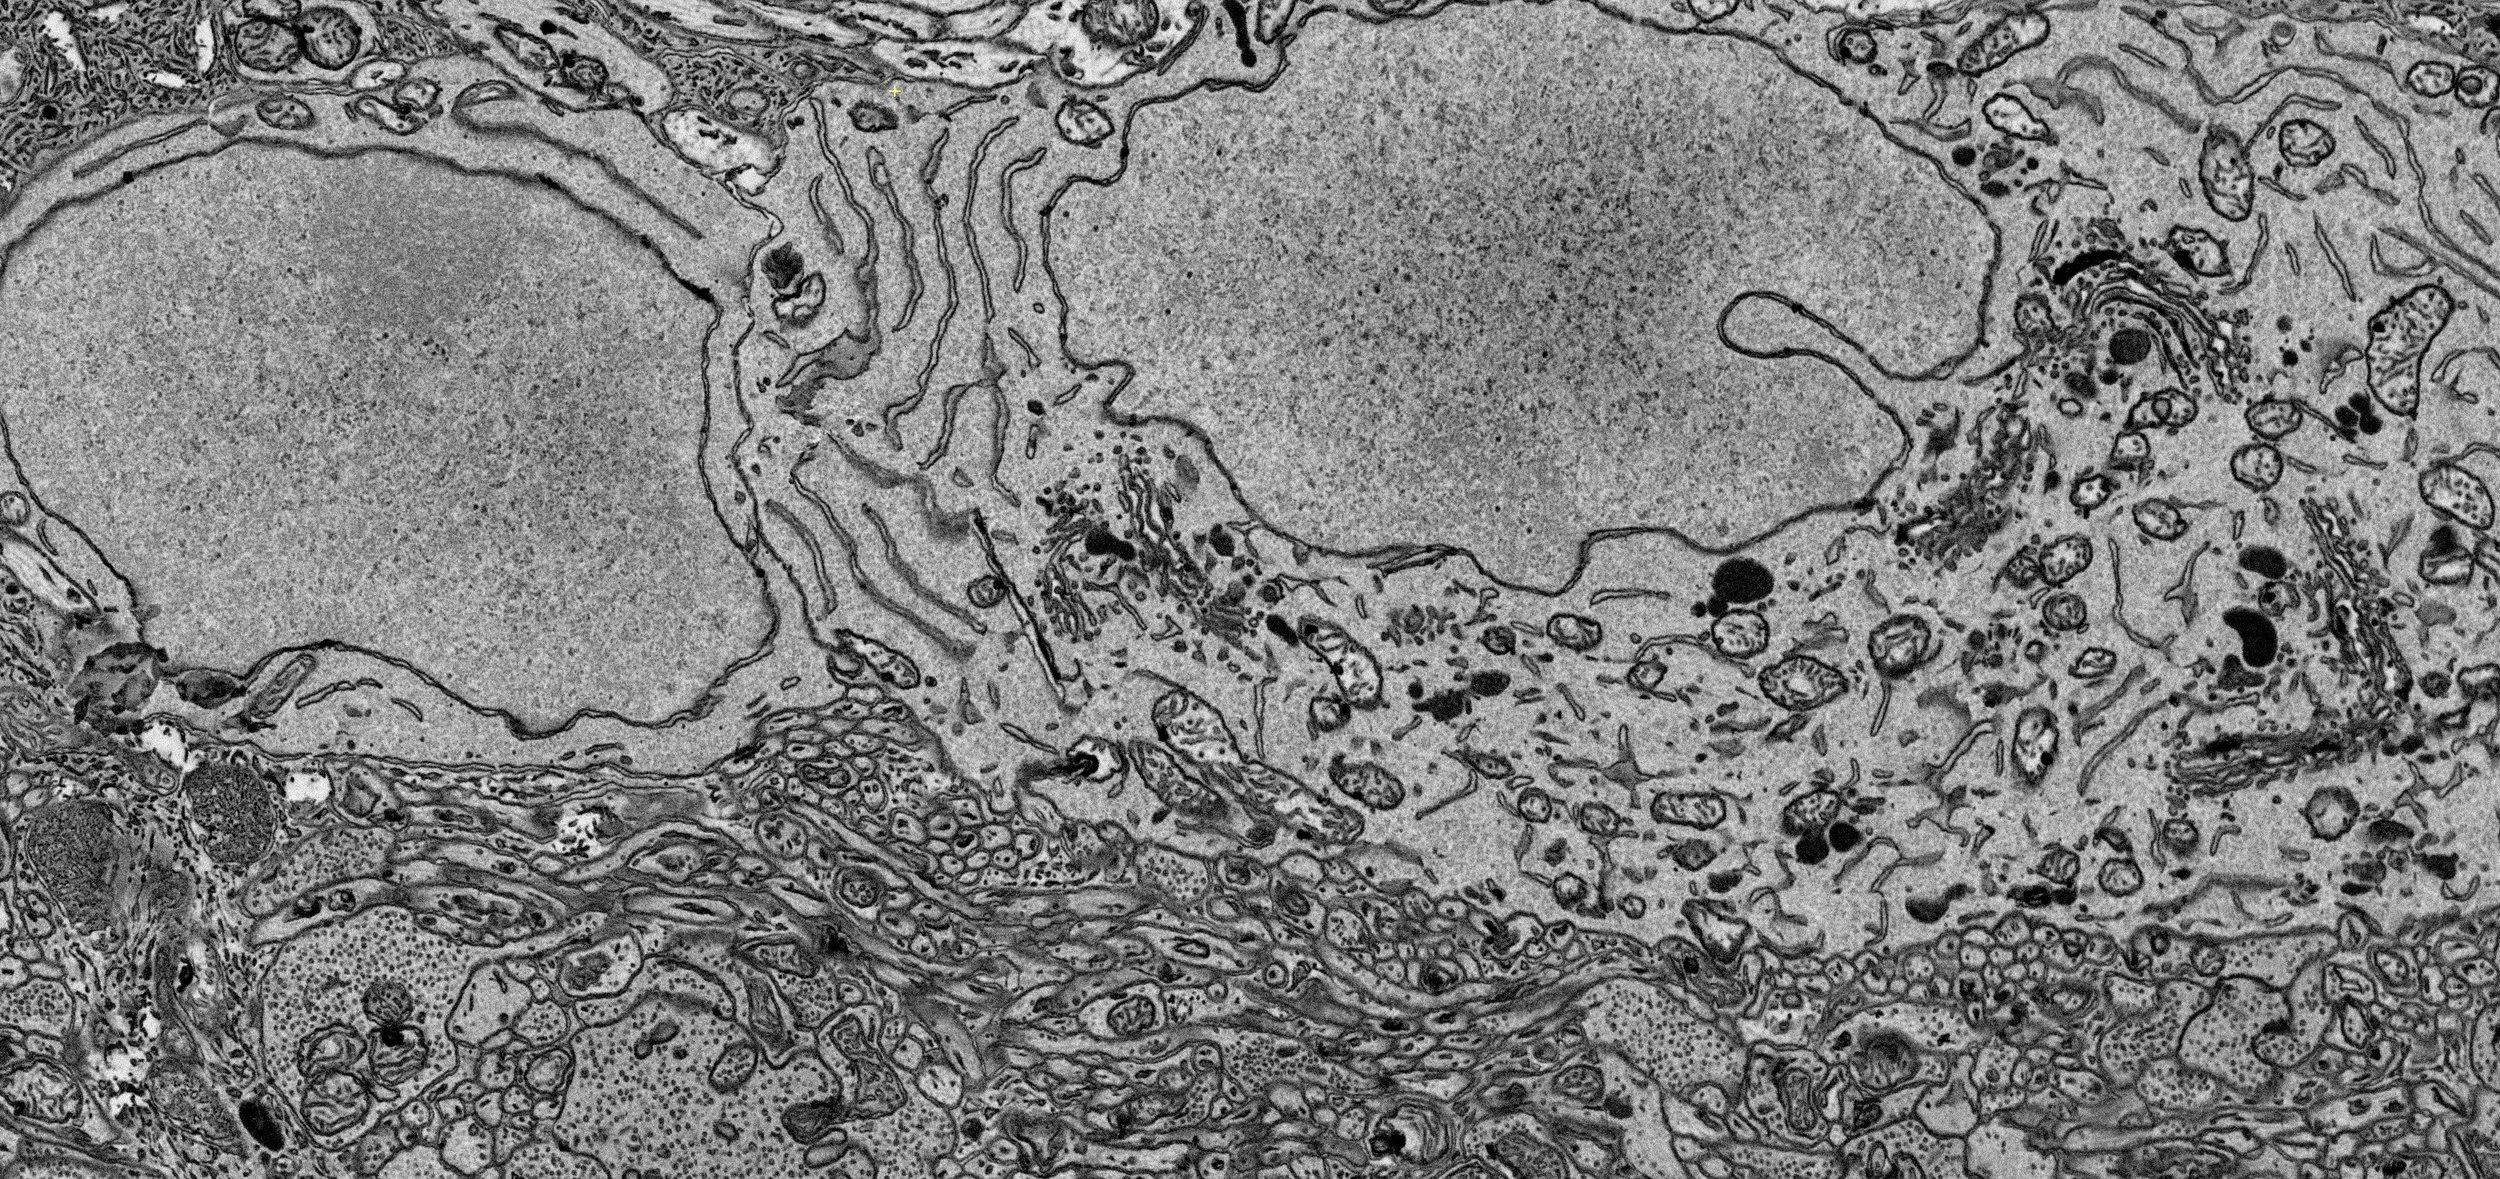

New review article “Glaucomatous optic neuropathy: Mitochondrial dynamics, dysfunction and protection in retinal ganglion cells” from our lab is now available online in Progress in Retinal and Eye Research.

Here, we review the current studies focusing on mitochondrial dynamics-based structural and functional alterations in the mitochondria of glaucomatous retinal ganglion cells (RGCs) and therapeutic strategies to protect RGCs against glaucomatous neurodegeneration. We thank you to all contributors.